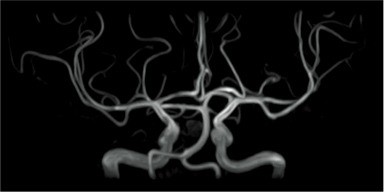

Subtraction of images with and without BeamSat pulses can be displayed in a reversed black-and-white image to visualize it as in MR-DSA.

Without BeamSat

With BeamSat

Subtraction image (reversed black-and-white image)